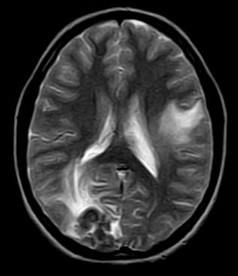

September 2005 - Intracerebral Tuberculomas

There is a conglomeration of lesions in the right temporo-parieto-occipital and left frontal lobes. These are hypointense on the T2W images and reveal a whorl or bunch of grapes type of enhancement. Note is made of perilesional edema.

On MRI

On plain MRI, granulomas usually appear isointense to gray matter on the T1W images and may have a slightly hyperintense rim (probably due to the presence of paramagnetic substances). On T2W images, the tuberculomas exhibit variable signal. They are often isointense or hypointense to brain parenchyma and it is postulated that this relative hypointensity is related to T2 shortening by paramagnetic free radicals produced by macrophages, which are heterogeneously distributed throughout the caseous granuloma. The diminished signal on T2W images may also be due to the mature tuberculoma being of greater cellular density than brain. Granulomas may also be hyperintense to brain on T2-weighted images; this is likely due to a greater degree of central liquefactive necrosis in these lesions. Edema surrounding tuberculomata is relatively more prominent in the early stages of granuloma formation.

Post contrast (gadolinium) images of TB granulomas demonstrate intense nodular and ring-like enhancement. Healed tuberculomas may calcify in up to 20% of cases and these are usually more evident on CT than MRI. On MRI, the calcifications are more evident on gradient-echo than on spin-echo imaging. Atrophy is frequently a long-term sequelae of tuberculous CNS infection. Full resolution of cerebral tuberculomas requires months to years of medical therapy. The length of time required is related more to the size of the original lesion than to any other single factor.